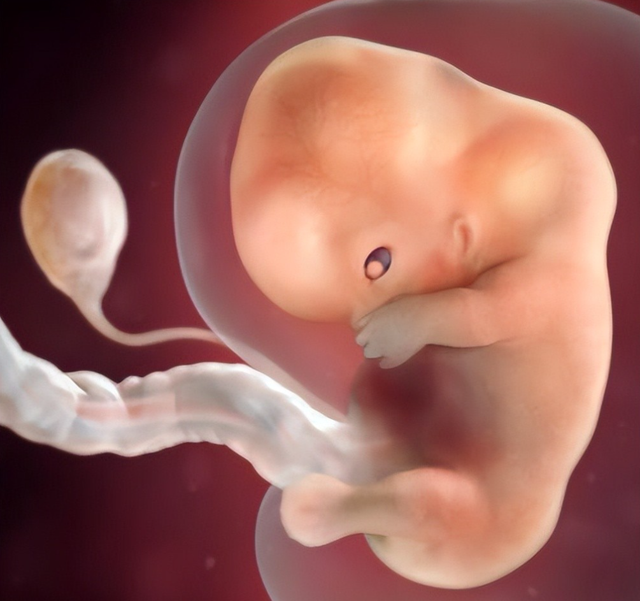

孕8周:看成出现

不错看到胚胎的手和脚,然则手指脚趾没长出来。

孕9周:头大身子小

先发育大脑,是以头相比大 ,身子看起来相比小。

孕10周:初具东谈主形

看得出胚胎是东谈主的形势。

孕11周:卵黄囊澌灭

胚胎前边一个大大的像气球雷同的卵黄囊,之前是提供养分的,然则冉冉的胎盘训诫了,这个卵黄囊就功遂身退了。